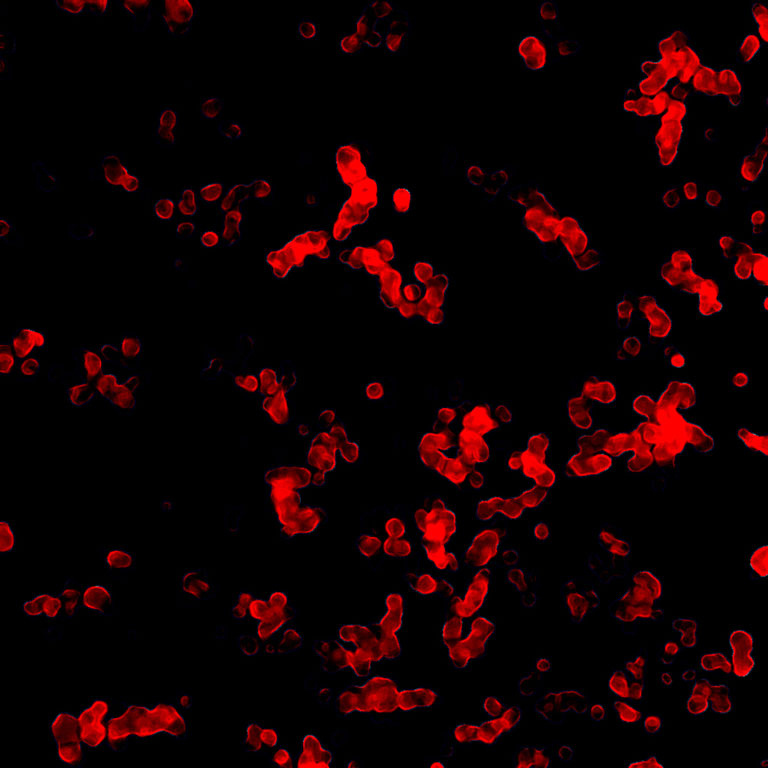

Spectral Scanning Confocal Fluorescence Microscopy

RNA interference (RNAi) therapy allows researchers to silence the expression of nearly any gene that leads to the production of a disease-associated protein. Although this novel method provides unprecedented therapeutic potential, effective packaging and delivery of short RNA sequences which facilitate RNAi remains a challenge due to their poor stability in the body and inefficient cellular uptake. Koch Institute researchers in the Hammond Lab are engineering RNAi technologies which consist of short RNAi sequences that self-assemble into sponge-like nanoparticles, each containing half a million drug molecules in a space more than 100 times smaller than the width of a human hair. These RNAi nanomedicines, which exhibit high stability and efficient cellular delivery, are currently being investigated as a means of silencing cancer-associated genes. These images demonstrate the morphology of RNAi nanosponges and also confirm the existence of fluorescently-labeled small interfering RNA within the structures.